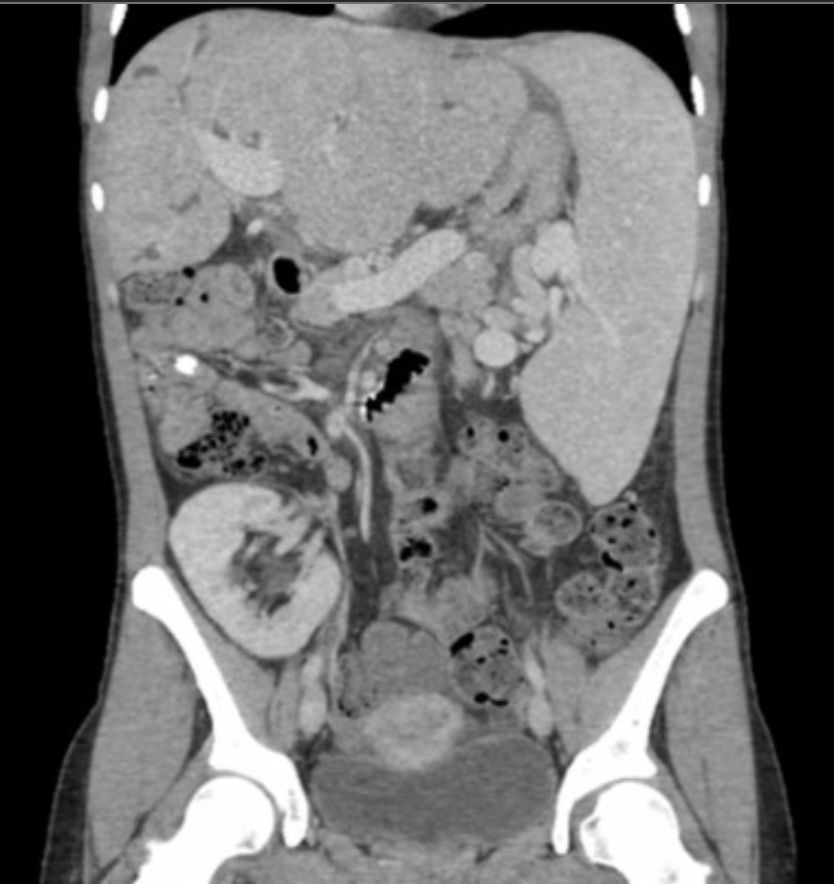

CT: hyperenhancement & thickening of bile duct walls often w/a CBD stone.

Tx: initially w/Abx & fluids, & if refractory, ERCP: stone removal & sphincterotomy.